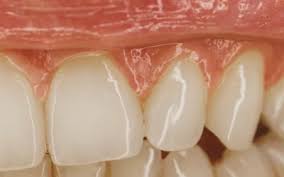

Diş Eti Çekilmesi: Nedenleri, Mekanizmaları ve Önleme Yöntemler Diş eti çekilmesi (gingival retraksiyon), dişeti dokusunun diş kökünden geri çekilmesiyle karakterizedir. Bu durum yalnızca estetik sorun yaratmakla kalmaz, aynı zamanda diş kökünün açığa çıkması nedeniyle hipersensitivite, çürük riski ve periodontal hastalık progresyonu gibi komplikasyonlara yol açabilir. Çekilmenin oluşumunda hem mekanik hem de biyolojik faktörler rol oynar.

- Periodontitis: Dişeti ve alveolar kemiğin kaybına yol açan ileri inflamasyon, diş eti çekilmesinin en yaygın biyolojik nedenidir.

- Periodontal cep oluşumu ve kemik kaybı, dişetinin diş kökü üzerinden geri çekilmesini kolaylaştırır.